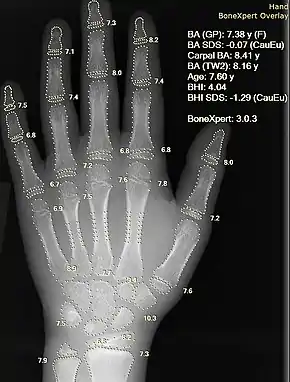

Information can take the form of images, sound, video or other multimedia. Bits of information can be streamed via signals. Its processing is the central notion of informatics, the European view on computing, which studies information processing algorithms independently of the type of information carrier – whether it is electrical, mechanical or biological. This field plays important role in information theory, telecommunications, information engineering and has applications in medical image computing and speech synthesis, among others. What is the lower bound on the complexity of fast Fourier transform algorithms? is one of unsolved problems in theoretical computer science.

| FFT algorithms | Image processing | Speech recognition | Data compression | Medical image computing | Speech synthesis |